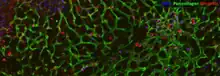

Liver tissue (PCLS) made and stained for immunofluorescence imaging.